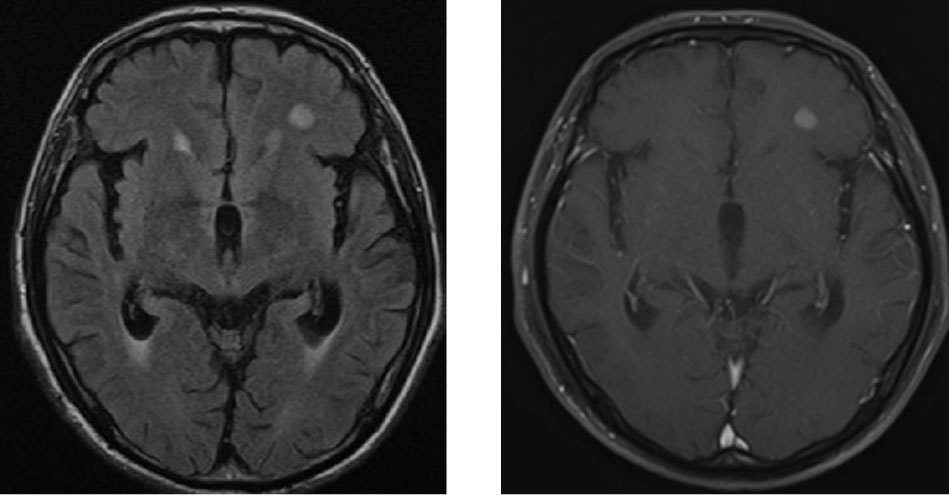

写真2: Nocardiaによる脳病変

左前頭葉に直径5mm程度の病変を認める (左:FLAIR、右:ガドリウム造影)